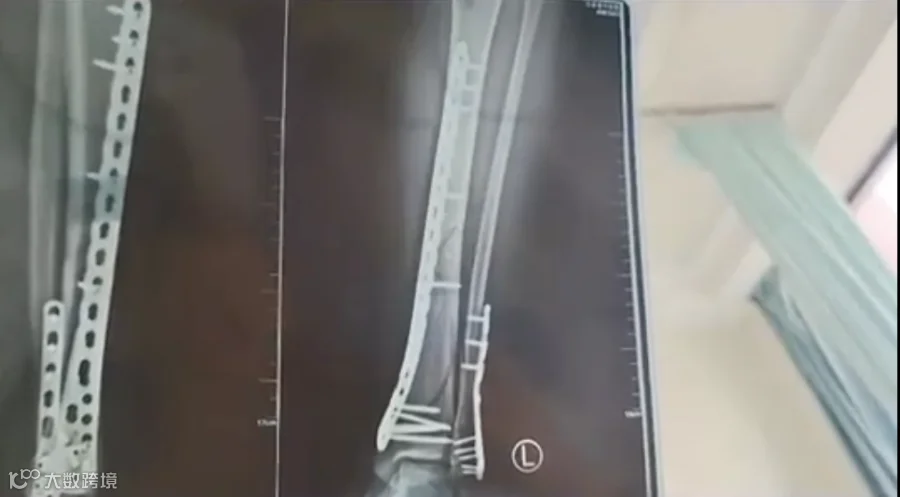

近日,甘肃兰州的武女士称母亲节当天,自己穿7cm厚洞洞鞋下楼,不慎崴脚摔倒,致使自己左腿粉碎性骨折。

该女子称,目前已做完手术在家休养,不过下地得拄拐才行,且下地有时间限制,不能久站,而骨折完全康复可能需要3个月,她提醒大家穿增高鞋要注意。